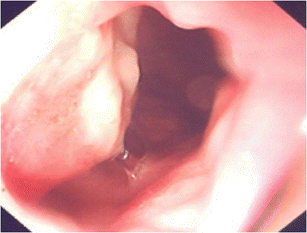

Fig. 1